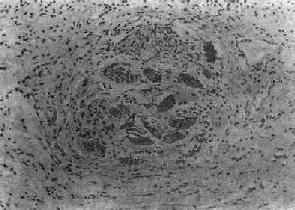

(2)慢性虫卵结节:急性虫卵结节经10余天后,虫卵内毛蚴死亡,坏死物质逐渐被吸收,虫卵破裂或钙化,其周围除类上皮细胞外,出现异物巨细胞和淋巴细胞,形态上似结核结节,故称为假结核结节(图19-7)。少数虫卵结节一开始即为假结核结节,而不经过急性虫卵结节阶段。最后,假结核结节中的类上皮细胞为纤维母细胞代替,并产生胶原纤维,使结节纤维化。其中央的卵壳碎片及钙化的死卵可长期存留。

图19-7 血吸虫病之慢性虫卵结节

结节中央有破裂和钙化的虫卵,其周围有类上皮细胞和异物巨细胞,形成假结核结节